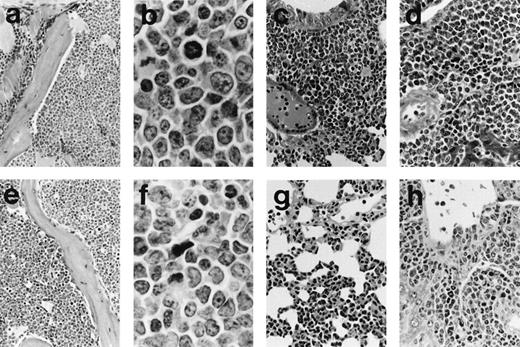

Histology of representative leukemias arising in MSCV-FL mice. Hematoxylin and eosin-stained sections are shown for mouse 196 with B-lymphoid leukemia (a through d) and for mouse 199 with biphenotypic leukemia (e through h). (a) The bone marrow architecture of mouse 196 is effaced by a blast cell infiltrate that extends into the adjacent muscle (original magnification × 185). (b) At higher magnification, blast cells in the bone marrow of mouse 196 can be seen to be predominantly medium-sized with round to oval nuclei, moderately basophilic cytoplasm, and occasionally with prominent nucleoli; mitotic figures are abundant (original magnification × 1,115). (c) Lung of mouse 196 showing diffuse interstitial and nodular peribronchial parenchymal infiltrates (original magnification × 270). (d) Liver of mouse 196 showing perivascular accumulations of blast cells as well as some blast cells around bile ducts (original magnification × 370). (e) Bone marrow of mouse 199 showing blast cells of variable size occupying the hematopoietic space; scattered erythroblasts and megakaryocytes are present (original magnification × 185). (f) At higher magnification, blast cells in the bone marow of mouse 199 of variable shape with irregular nuclei and one to three distinct nucleoli can be seen to be intermixed with granulocytic cells of various maturational stages (original magnification × 1,115). (g) Lung of mouse 199 showing diffuse interstitial infiltrates of blast cells and granulocytes (original magnification × 270). (h) Liver of mouse 199 showing polymorphous tumor infiltrates, sometimes with pronounced granulocytic differentiation, mainly in periportal areas (original magnification × 370).

Histopathological and flow cytometric evaluation of tissues taken at postmortem and serial transplantation showed that the MSCV-FL mice had developed B-cell and/or myeloid leukemias. Splenomegaly (∼5-fold enlargement; average spleen weight of 0.48 ± 0.05 gv 0.09 ± 0.02 g in controls), invasion of the lungs and liver (Fig 3), and colonization of the bone marrow by the tumors were frequently observed, along with some lymph node infiltration (see Fig 8) but no or minimal involvement of the thymus. The phenotype of representative leukemias was evaluated by immunofluorescence flow cytometric analysis of spleen cell suspensions using monoclonal antibodies recognizing hematopoietic cell surface antigens. The analysis demonstrated heterogeneous expression of markers characteristic of the B-lymphoid and myeloid lineages, including the B-lineage marker B220/CD45R, the myeloid differentiation antigen Mac-1/CD11b, the granulocyte marker Gr-1/Ly-6G, and the monocyte/macrophage differentiation antigen Ly-6C, as well as low-affinity Fc receptors for IgG FcγRII/III and the heat-stable antigen HSA/CD24 found on cells belonging to both lineages (data not shown). Although the heterogeneity was likely due in part to reactive cells, double staining with antibodies against B220 and Mac-1 showed a minor subpopulation in some of the tumors that was positive for both markers (Fig 4), suggesting that, in these cases, a precursor common to the B-cell and myeloid lineages was the target cell for transformation. To further investigate this possibility, we transferred serially transplanted tumors to culture (see Materials and Methods). Three of the four leukemic populations studied in detail (196-, 199-, and 203-series cells) preferentially expressed B220 or Mac-1 after several weeks in vitro, whereas the majority of cultured 204-series cells coexpressed B220 and Mac-1 (Table 2).